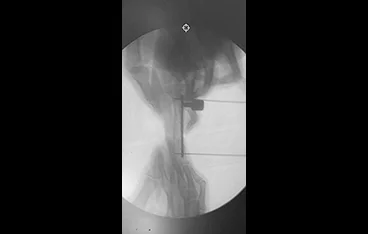

• 최소침습 골절수술